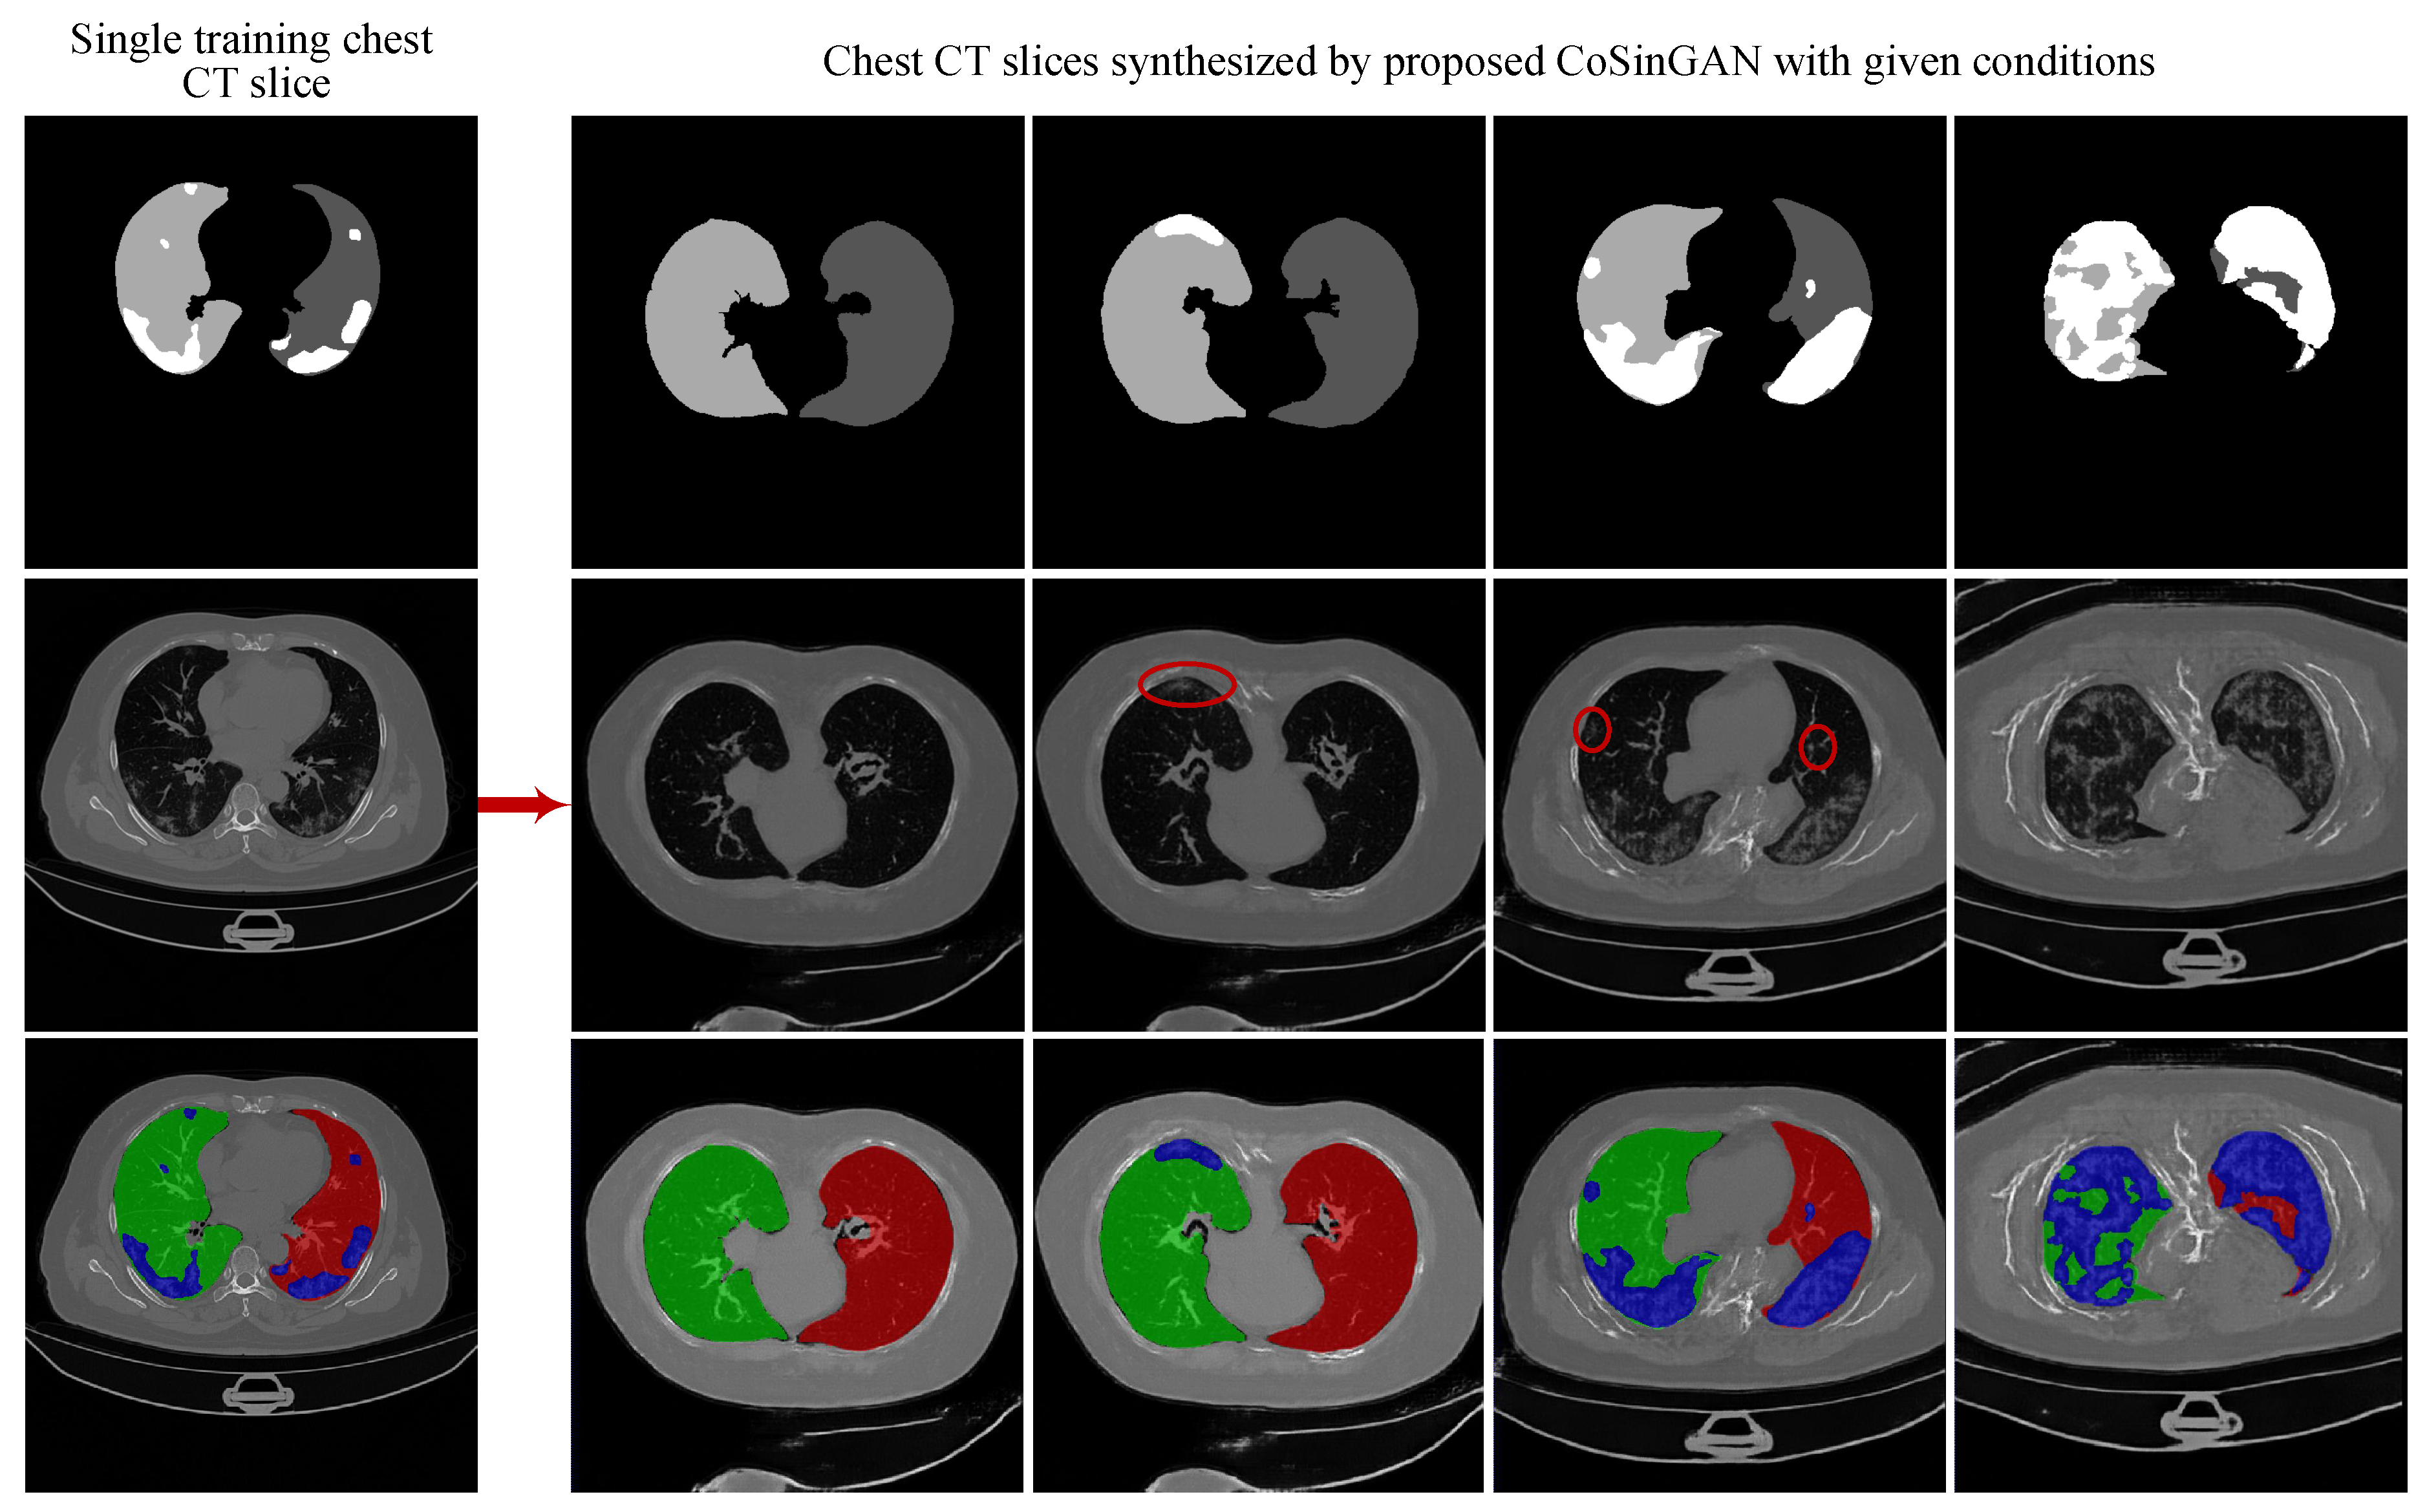

3.1.4. Evaluation on the Ability of CoSinGAN in Generating Diverse Samples